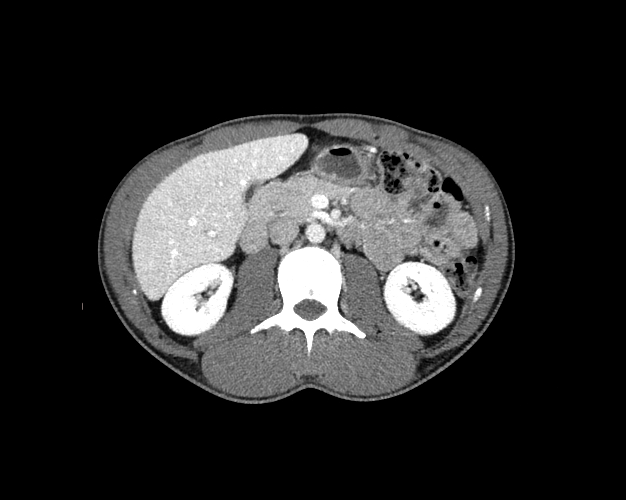

Body

Covers abdominal CT anatomy.